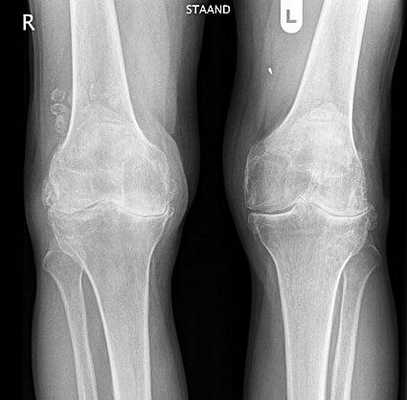

д) Рентгенологическое обследование включает полноразмерные рентгенограммы конечности целиком, рентгенограммы коленного сустава стоя в переднезадней проекции, в заднепередней проекции при сгибании, боковой проекции и проекции Merchant (рис. 1)

е) Рентгенограммы в боковой проекции должны быть высокого качества и обеспечивать возможность диагностики дисплазии блока (описанные DeJour симптом пересечения, надблоковая шпора и двойной контур) (рис. 2)

Гонартроз обоих коленных суставов.